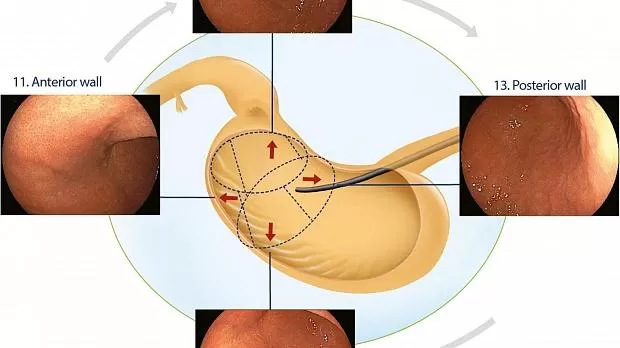

Нижняя треть

После оттягивания назад дистальная треть исследуется по часовой стрелке с четырьмя изображениями крупным планом с прицелом, ориентированным по оси желудка, где большая кривизна расположена в нижней части эндоскопического поля: передняя стенка, включая переднюю часть режущего края. angularis, область 11; меньшая кривизна, где выпуск воздуха позволяет его захват, более вертикально ориентированный, область 12; задняя стенка, включая заднюю часть угловой вырезки, область 13; и большая кривизна, где часто видна эпителиальная переходная зона, область 14 (рис. 5 ).